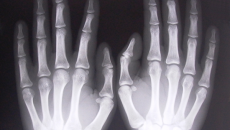

Ученик с 28 импланта в гръбначния стълб се озова в ареста в Перник след фалшиво положителен тест за наркотици